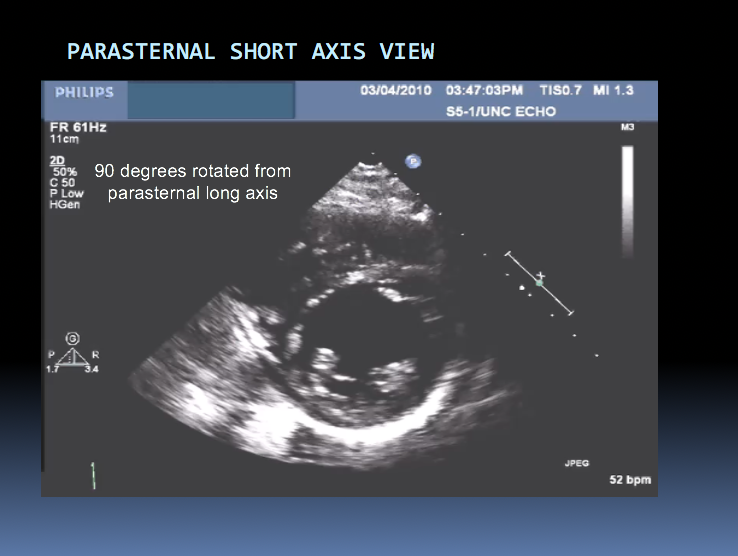

Have 2 primary probe positions, with multiple angulations (multiple ultrasonic beams are transmitted from transducer through a wide arc). The returning signals are integrated to produce 2D images of the heart on a video monitor.

Identify the chambers shown in this image: